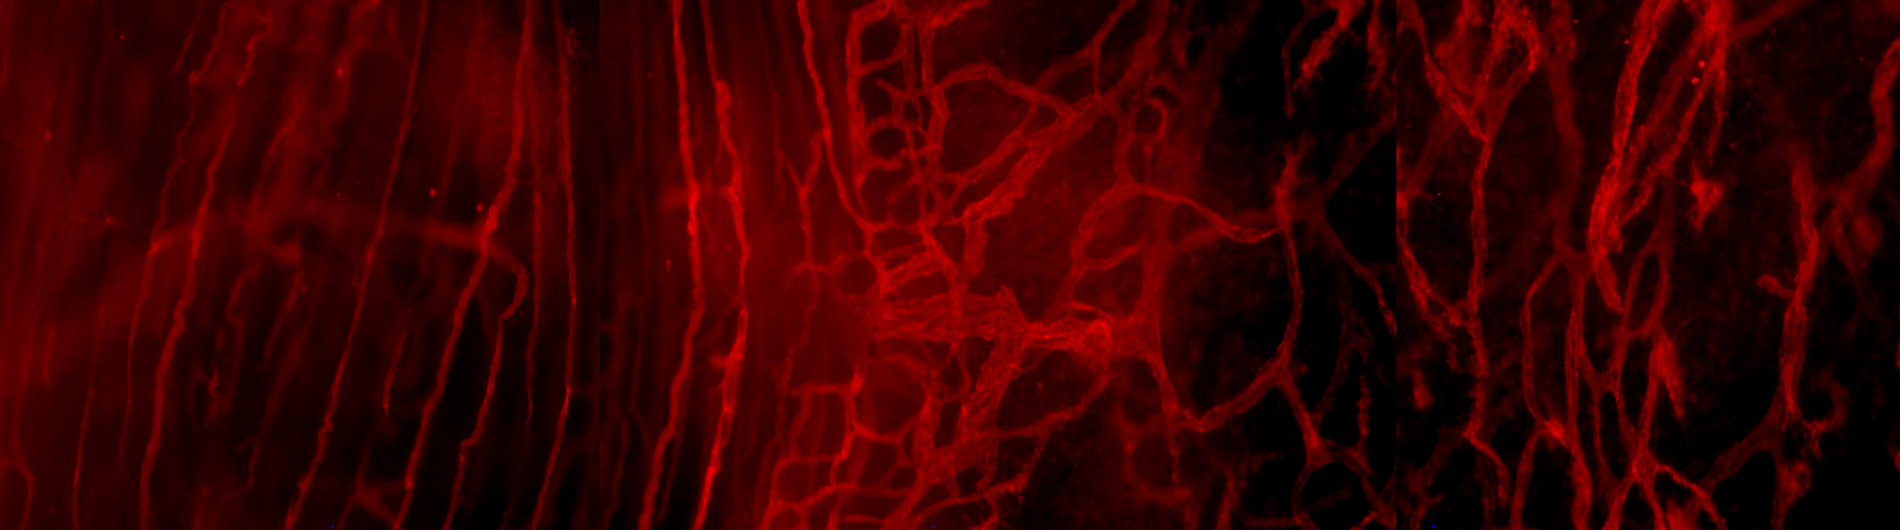

Crosstalk between the Nervous and Immune Systems within the Tumor

Uccello TP, Lesch ML, Ullman NA, Kintzel SA, Gradzewicz LB, Velagaleti T, Fleming FJ, Mills BN, Murphy JD, Garrett-Larsen J, Qiu H, Drage MG, Ye J, Gavras NW, Johnston CJ, Love TMT, Repasky EA, Linehan DC, Lord EM, Gerber SA. Radiation Therapy Exacerbates Tumor-Promoting Innervation and Nerve Signaling in Rectal Cancer. Int J Radiat Oncol Biol Phys. 2023 Mar 1;115(3):733-745. doi: 10.1016/j.ijrobp.2022.09.080. Epub 2022 Oct 4. PubMed PMID: 36202180; PubMed Central PMCID: PMC9898185.